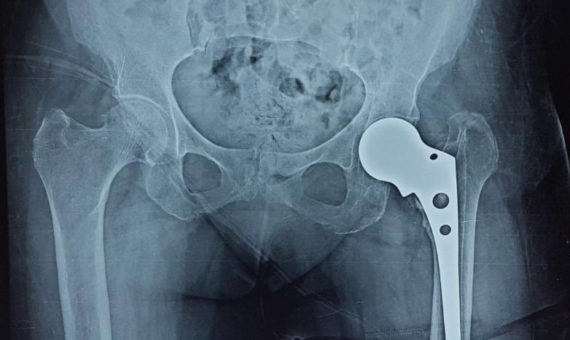

A 75 years old female from Neemuch presented to us following a fall and broken femur. She had alread [...]